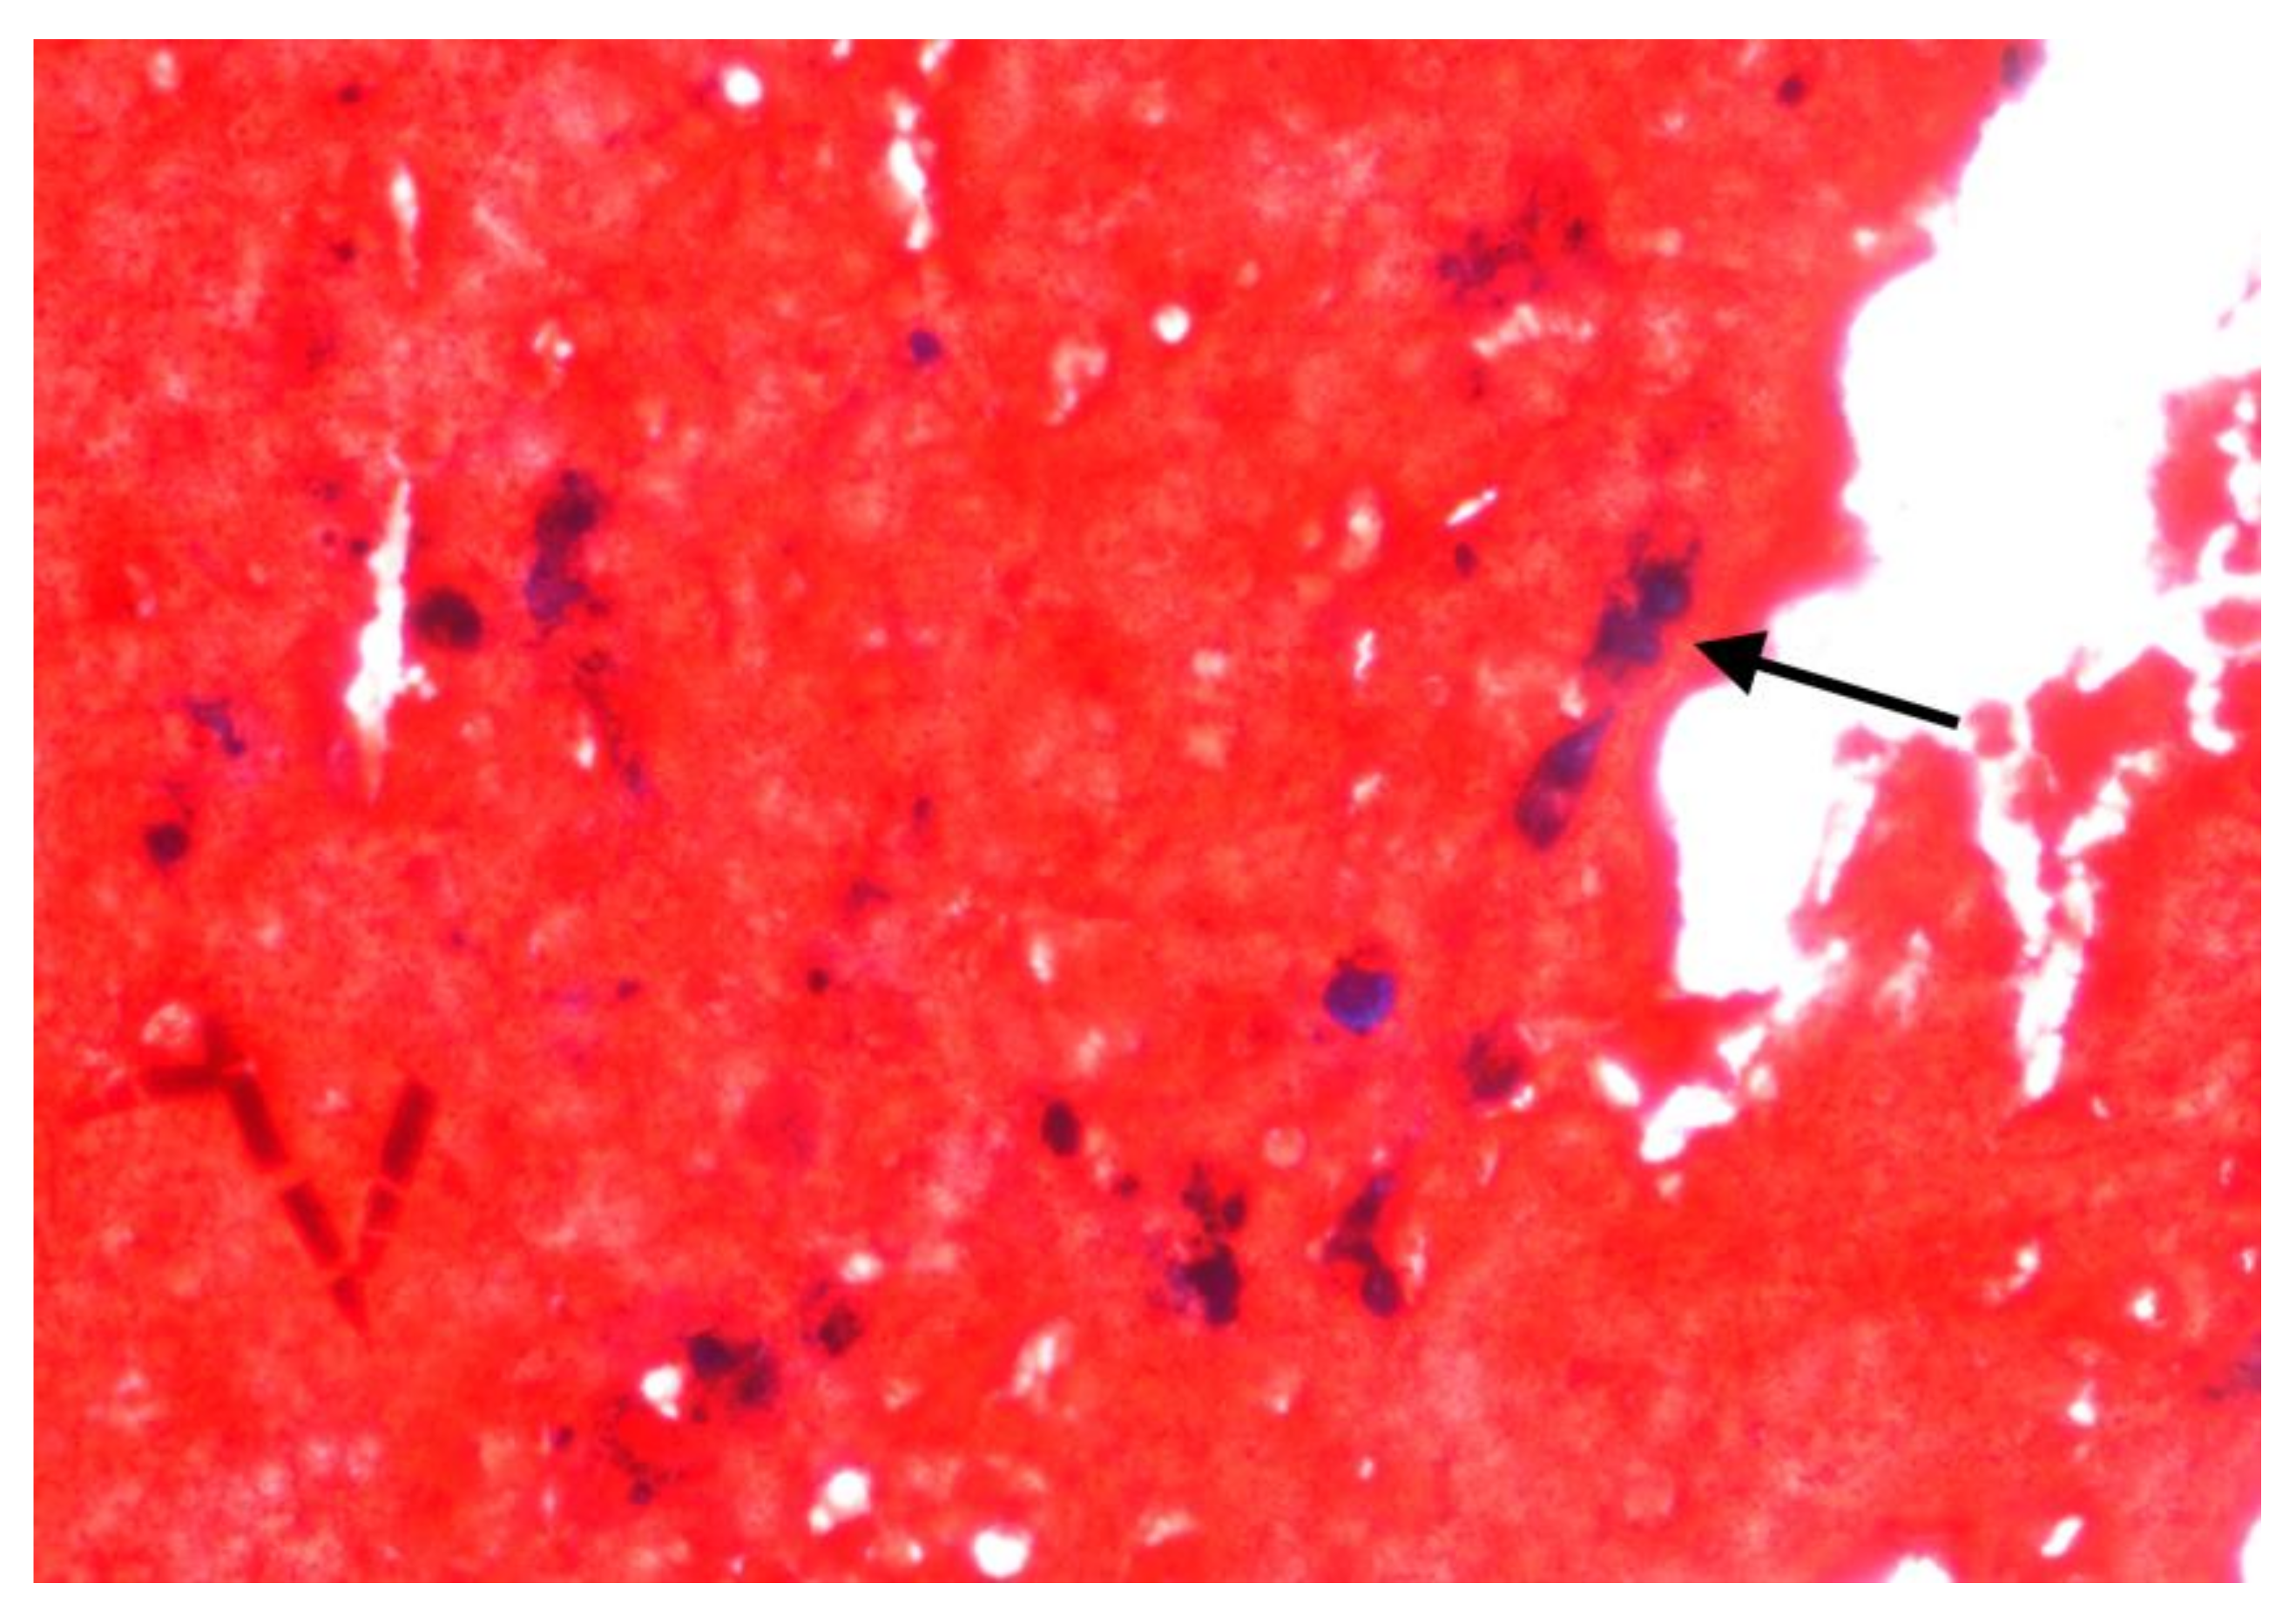

| 1 * | Epithelioid mesothelioma | Pleura | - | Score 0 (0%) | 70% | 12% | Palliative |

| 2 ** | Epithelioid mesothelioma | Pleura | - | Score 3 (60%) | 44% | 54% | Palliative |

| 3 ** | Biphasic (Epithelioid adenomatoid/solid 80%) mesothelioma | Peritoneum | - | Score 3 (55%) | 90% | 10% | Palliative |

| 4 * | Biphasic (Epithelioid solid/trabecular 70%) mesothelioma | Peritoneum | - | Score 0 (0%) | 75% | 20% | Palliative |